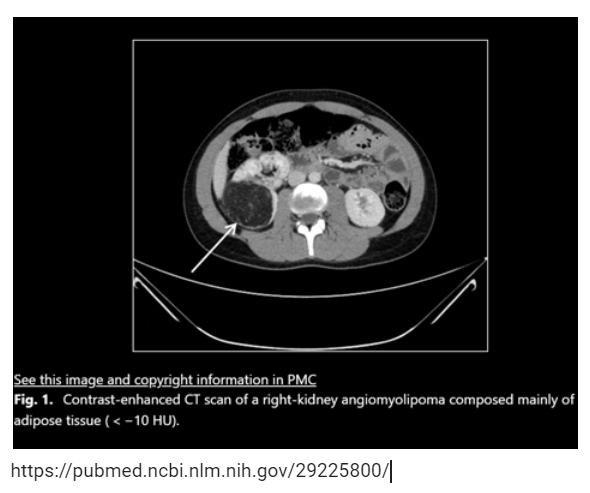

Ans: Angiomyolipoma

📌Rare Benign renal masses

📌80% with syndromes: TS, VHL, SW, NF, ADPKD

📌Macroscopic fat in CT/MRI

📌asymptomatic & <4cm➡️biannual/ annual follow-up with US/CT

📌Symptomatic or ≥4cm or B/L➡️surgery or arterial embolization